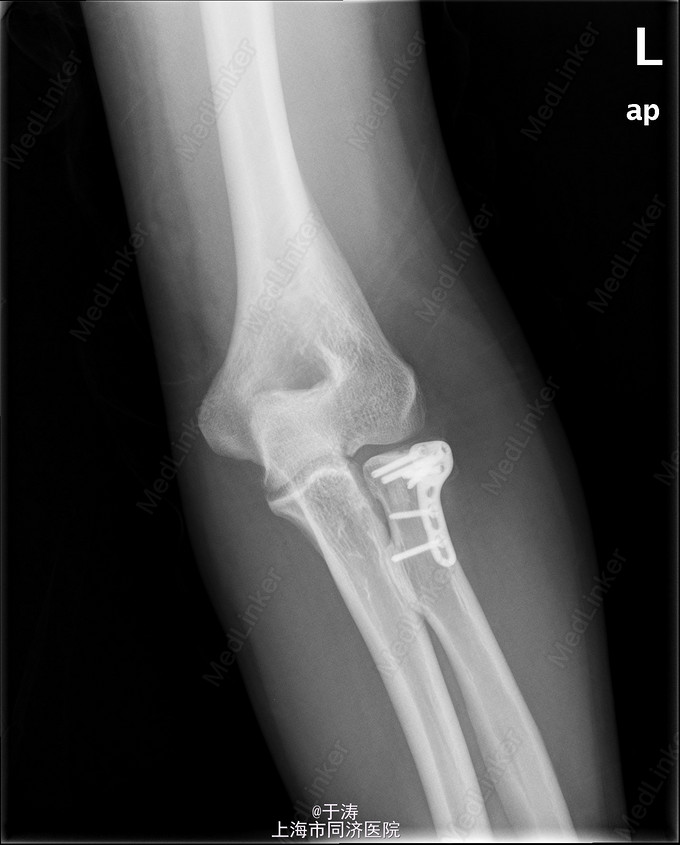

查体:左肘肿胀明显,桡骨头部压痛,关节活动受限,被动活动时疼痛加剧。摄X线及CT示左桡骨头骨折。

诊断为左桡骨头骨折 予完善围手术期准备后行左桡骨头骨折切开复位内固定术。

患者术后16月随访,骨折愈合良好,力线良好,关节面平整,活动可。桡骨头对于前臂旋转和肘关节活动具有重要意义,ORIF术可获得良好效果。